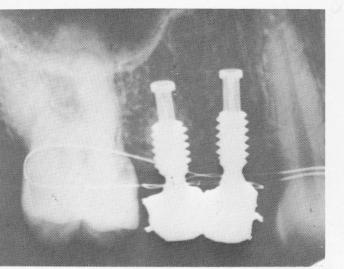

Fig. 8-14. A postoperative intraoral radiograph showing the acrylic-over-gold splint cemented over the implant shafts on the right side of the maxilla.

Fig. 8-15. The final prostheses cemented over the implants on the left side. Note the stainless steel .010 dead soft ligature wire used for temporary stabilization.

3 Endosseous implant prostheses cemented,ligature wire for stabilization

5 Acrylic-over- old splint over endosseous implant shaft on maxilla